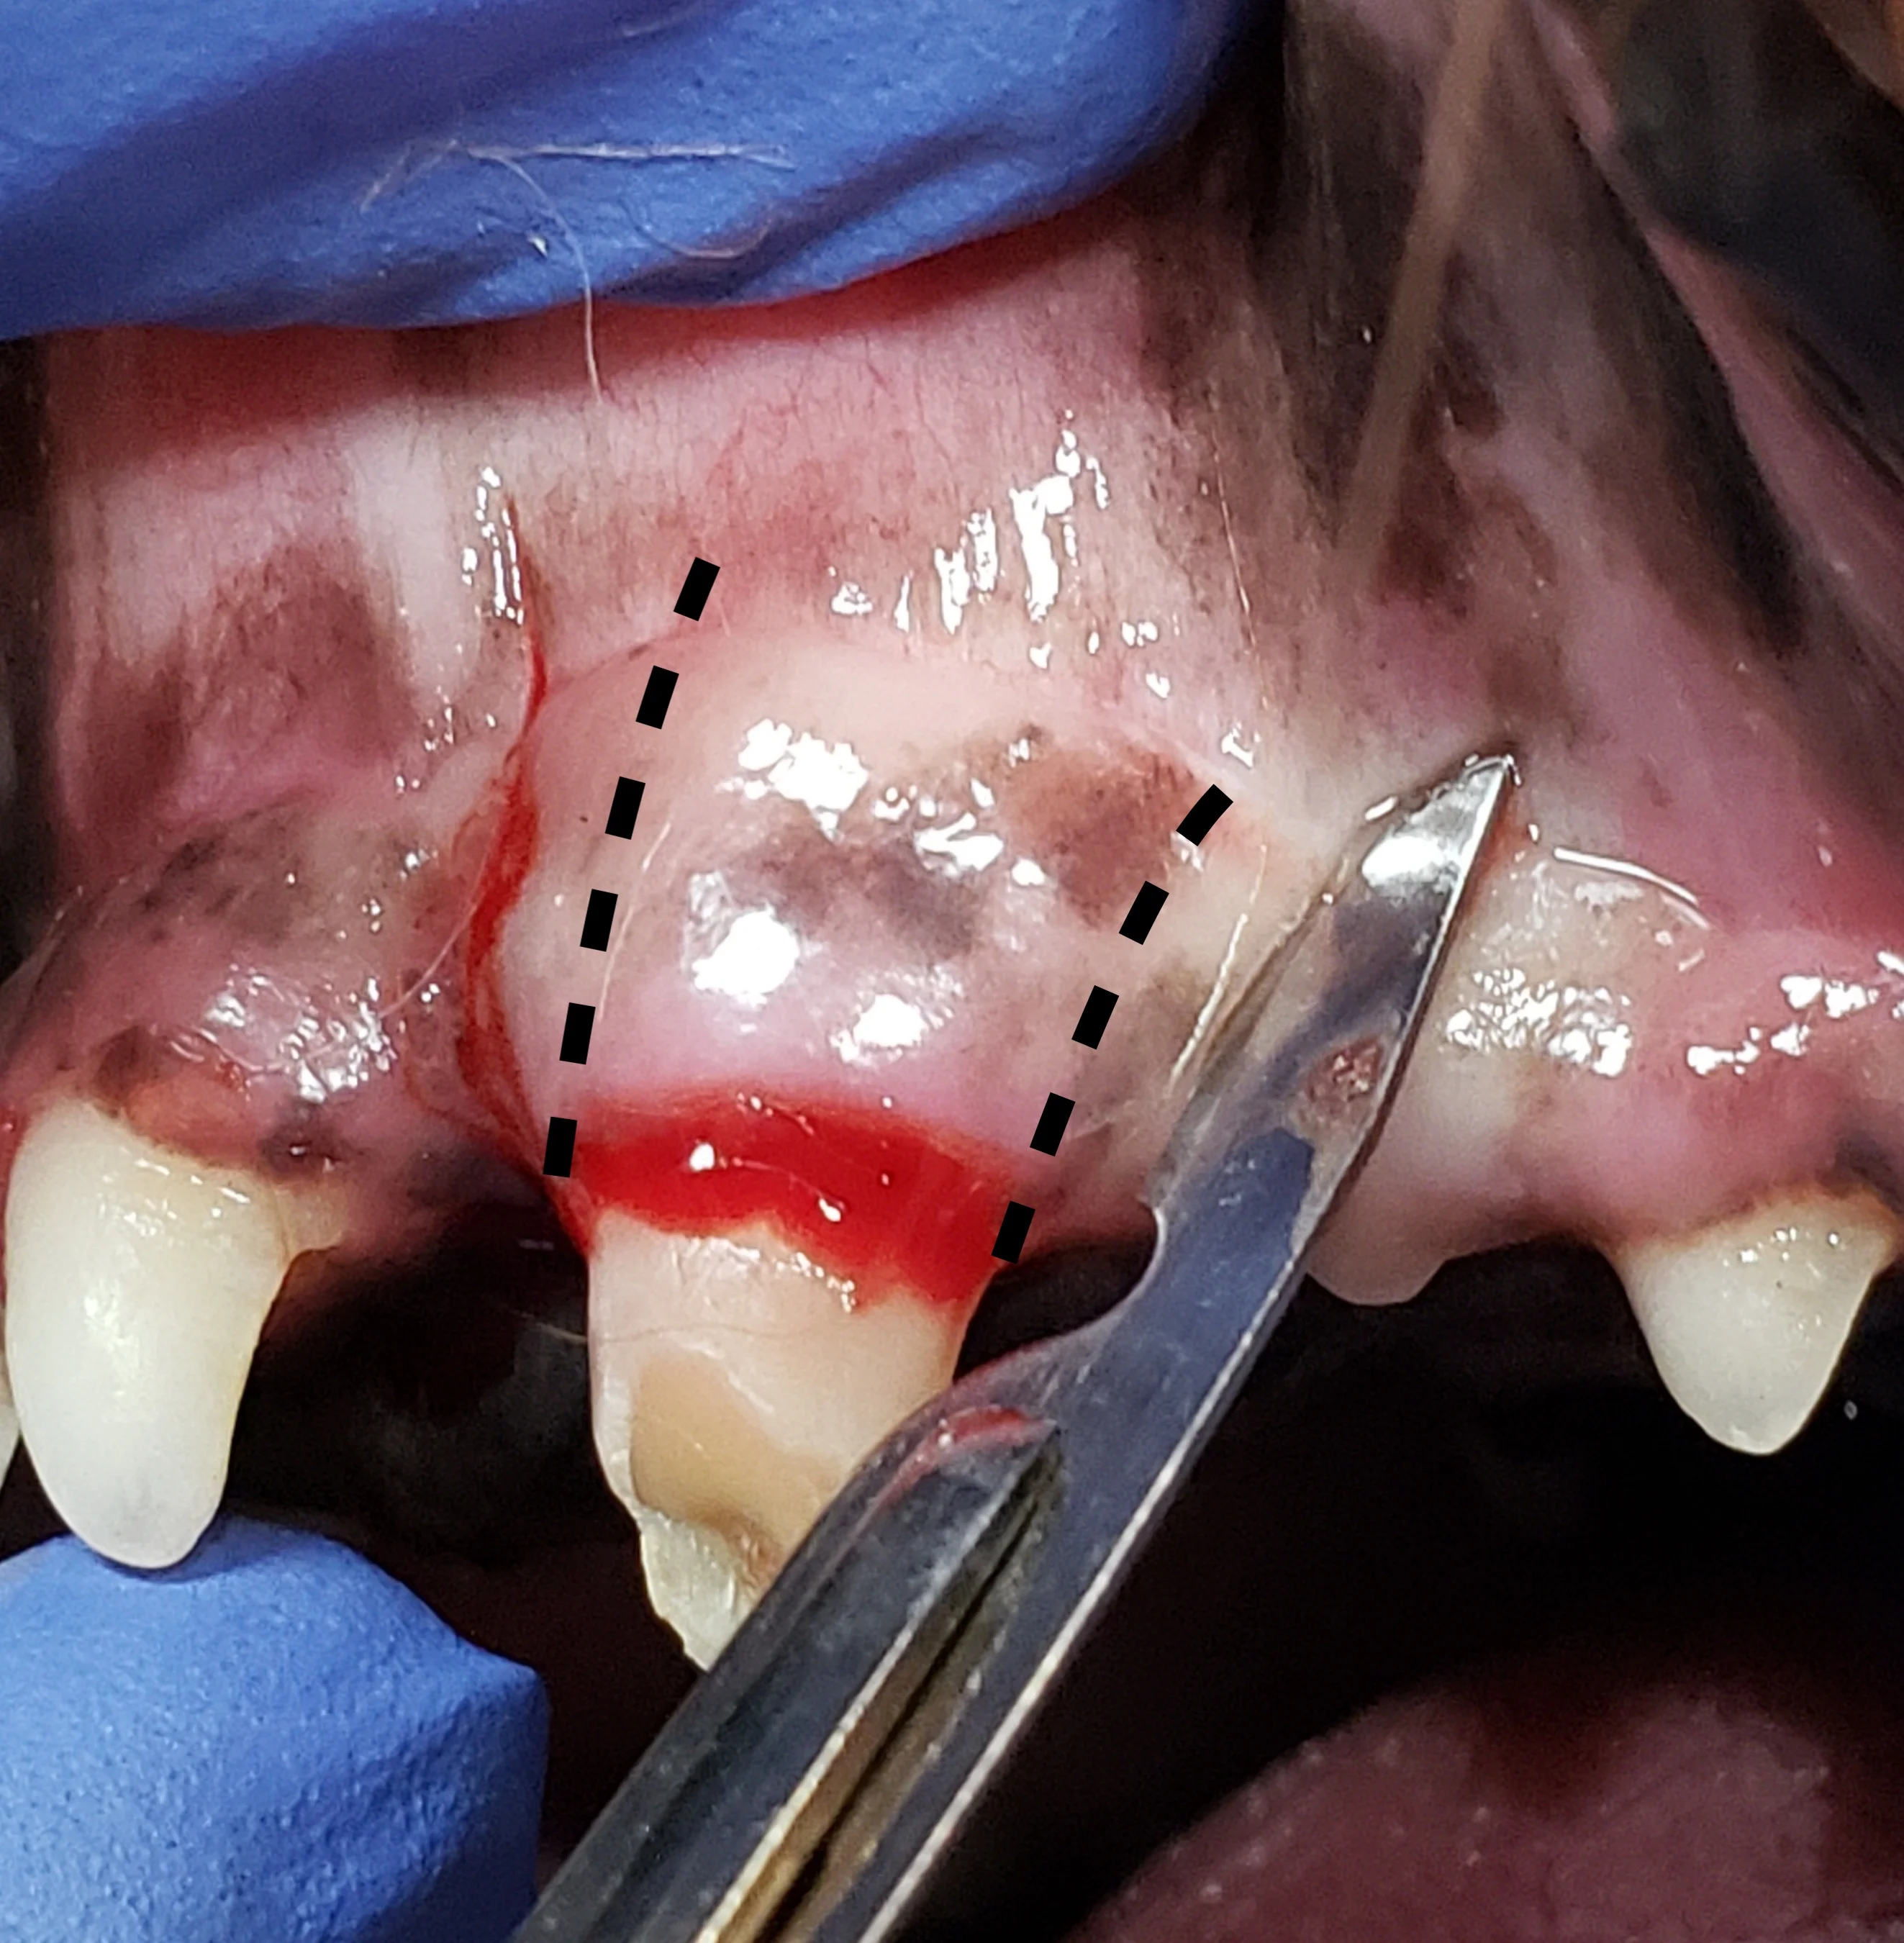

Step 2: Make Gingival Flap Releasing Incisions

Make releasing incisions for a full-thickness mucoperiosteal flap through the attached gingiva, past the mucogingival line, and at least a couple of millimeters into the alveolar mucosa to provide adequate exposure.

Rectangular Flap

A rectangular flap is created by making a mesial incision and a distal incision angled away from the tooth, following the distally curving position of the root. Releasing incisions should extend at least to the level of the widest part of the root and should be slightly divergent from each other, keeping the alveolar mucosa at the base of the flap wider than the coronal aspect with the attached gingiva, to provide enough tissue for closure. A flap wider at the gingival margin is important if an oronasal fistula is present. Making releasing incisions 1 to 2 mm from the outline of the tooth edge (dotted lines) places the incisions over bone, enhancing access to the periodontal ligament space and supporting the suture line following closure. In the author’s experience, this flap design provides optimal accessibility for tooth elevation and does not result in disruption of blood supply during healing.